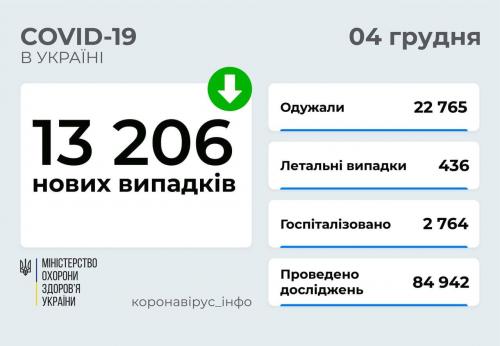

МОЗ: Уперше з початку пандемії було зроблено понад 100 тисяч ПЛР-досліджень за добу

Пів тисячі - у важкому стані, 9 жителів Рівненщини померли за добу від коронавірусу